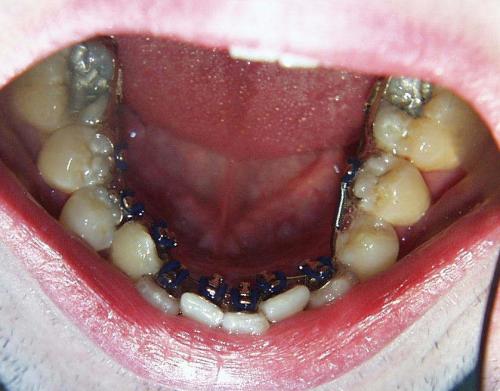

Während der Behandlung

Bild 1: Einsetzen der Lingualapparatur; der kleine Backenzahn ist bereits entfernt.